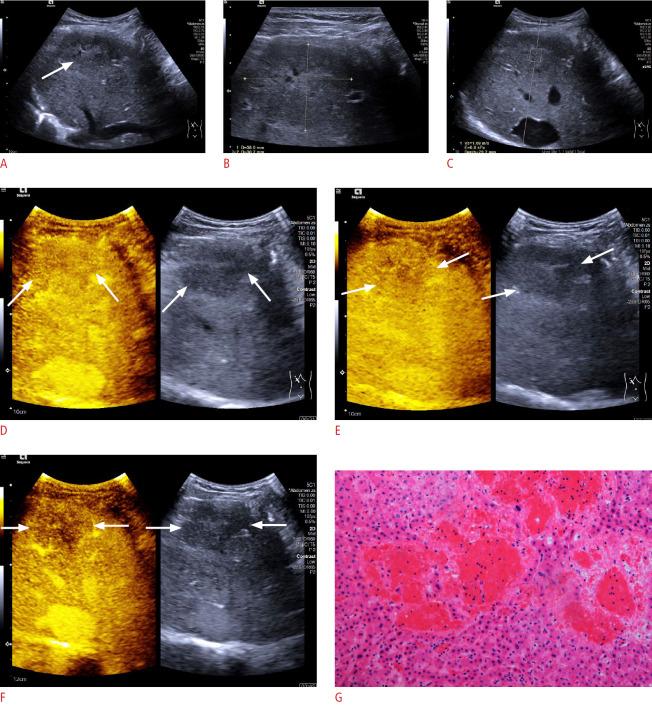

Ultrasound findings in peliosis hepatis.

The mean size was 36.8±12.4 mm (range, 10 to 80 mm). On B-mode ultrasonography (BMUS), all PH lesions were heterogeneously hypoechoic, with well-defined margins but irregular shapes. No mass effect was observed. During the arterial phase of CEUS, all lesions displayed mild heterogeneous hyperenhancement (83.3%, 20/24) or isoenhancement (16.7%, 4/24). Furthermore, 87.5% of the PH lesions showed mild washout after 1 minute in the portal venous phase (30-120 seconds) and mild washout in the late phase (>120 seconds).

The lack of a mass effect on BMUS, mild heterogeneous arterial hyperenhancement, and washout in the very late portal venous phase (after 1 minute) on CEUS are characteristic of PH. Although it is a histological diagnosis, PH should be considered in the differential diagnosis when the clinical context does not favor a malignancy or infection.

病变平均大小为36.8±12.4mm(范围10至80mm)。在B型超声(BMUS)检查中,所有PH病变均为不均匀低回声,边界清晰但形状不规则,未观察到占位效应。在CEUS动脉期,所有病变均表现为轻度不均匀高增强(83.3%,20/24)或等增强(16.7%,4/24)。此外,87.5%的PH病变在门静脉期(30 - 120秒)1分钟后表现为轻度消退,在延迟期(>120秒)表现为轻度消退。

BMUS无占位效应、CEUS动脉期轻度不均匀高增强以及门静脉期极晚期(1分钟后)消退是PH的特征。虽然PH是一种组织学诊断,但当临床情况不支持恶性肿瘤或感染时,在鉴别诊断中应考虑PH。